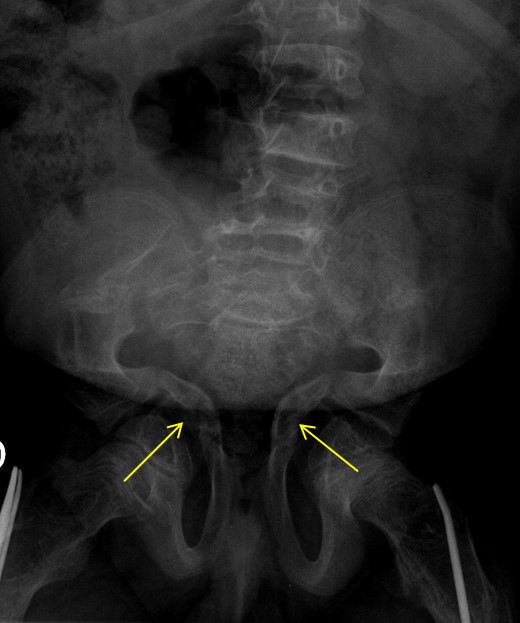

- Acetabular protrusion: This condition involves the hip joint protruding into the pelvic region (refer to Figure 14), where vital organs such as the intestines and bladder are situated. The compression exerted by the femoral head on these organs can lead to abdominal pain, constipation, and other related symptoms. Managing this complication is challenging, and current reported outcomes have been less than satisfactory. Generally, conservative approaches are employed, focusing on methods to regulate constipation. In severe cases, where intestinal obstruction hinders normal bowel movement, a colostomy may be required. A colostomy is a surgical procedure that redirects the terminal part of the intestine towards the abdominal wall, allowing for the elimination of faeces, which are collected in a bag attached to the abdomen.